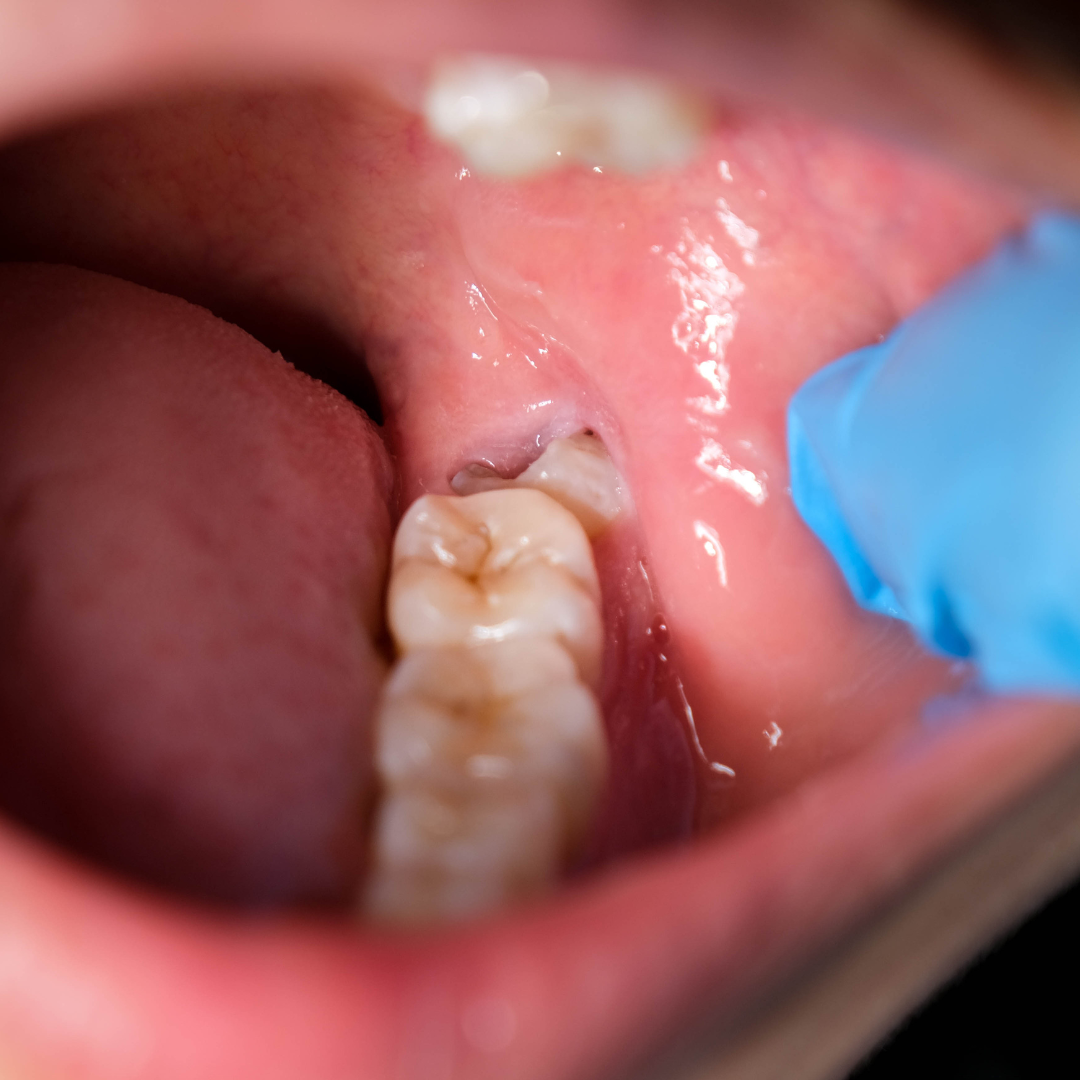

ฟันคุดอักเสบ เหงือกบวม ปวดกราม เชียงใหม่ | infected wisdom tooth and gum swelling chiangmai

ฟันคุด คือ ฟันที่ไม่สามารถขึ้นมาได้ตามปกติในช่องปาก เนื่องจากมีสิ่งกีดขวางการขึ้น การสร้างหน่อฟันผิดตำแหน่ง หรือการขาดพื้นที่ให้ขึ้น มักพบบ่อยที่ฟันกรามซี่สุดท้าย (หรือฟันกรามแท้ซี่ที่สาม) และบางครั้งอาจพบที่ฟันเขี้ยวได้ด้วย ฟันคุดอาจพบได้ทั้งแบบที่โผล่พ้นเหงือกขึ้นมาบางส่วน หรือไม่พบในช่องปากเลย

ฟันกรามซี่ที่สามที่ฝังคุด หรือที่คนเหนือเรียกกันว่า “ฟันเขี้ยวซาว” เป็นฟันกรามแท้ซี่สุดท้ายในช่องปาก โดยทั่วไปจะเริ่มขึ้นเมื่ออายุ 17 ปีขึ้นไป สำหรับคนที่มีพื้นที่ขากรรไกรเพียงพอ ฟันซี่นี้ก็จะขึ้นมาในช่องปากได้ตามปกติ แต่หากมีพื้นที่ไม่พอ หรือแนวการขึ้นของฟันเอียง อาจทำให้เกิดลักษณะที่เรียกว่าฟันคุดได้ คนไข้ที่มีฟันกรามซี่ที่สามฝังคุด มักจะรู้สึกปวดบริเวณฟันด้านในสุดเป็น ๆ หาย ๆ และหากฟันคุดโผล่ขึ้นมาบางส่วน อาจมีเศษอาหารติดบริเวณนั้น ส่งผลให้ฟันข้างเคียงผุได้ด้วย หากท่านมีอาการเหล่านี้อยู่ สามารถให้ทันตแพทย์ตรวจทางคลินิกและถ่ายเอกซเรย์ได้ เพื่อวางแผนการรักษาหรือเฝ้าระวังแต่เนิ่น ๆ

ฟันกรามซี่ที่สามที่สามารถขึ้นมาได้บางส่วนและมีลักษณะเอียง อาจทำให้มีเศษอาหารติดระหว่างฟันคุดกับฟันข้างเคียง ซึ่งเป็นบริเวณที่ทำความสะอาดได้ยาก ส่งผลให้เกิดฟันผุบริเวณซอกฟันข้างเคียง และอาจทำให้มีกลิ่นปากตามมาได้

• เหงือกบวมและปวดเป็น ๆ หาย ๆ

เนื่องจากฟันคุดทำความสะอาดได้ยาก บางครั้งอาจมีเศษอาหารตกค้างอยู่โดยไม่รู้ตัว ทำให้เกิดการสะสมของแบคทีเรียและคราบหินปูน จนนำไปสู่การติดเชื้อ และพัฒนาเป็นโรคเหงือกอักเสบรุนแรงได้ อาการอาจรวมถึงเหงือกบวมแดง มีหนอง เป็นไข้ เจ็บคอ กลืนน้ำลายลำบาก และอ้าปากไม่ได้ หากสังเกตว่าเหงือกบริเวณฟันคุดมีอาการบวม ควรรีบพบทันตแพทย์เพื่อรับการตรวจโดยเร็ว